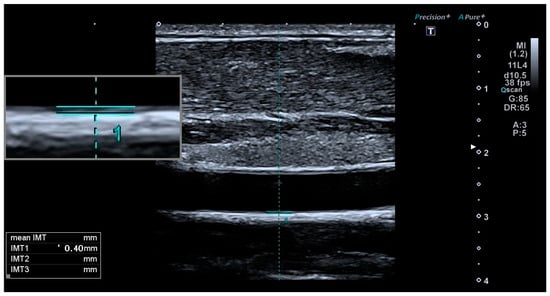

| Internal-CIMT (mm) | 0.7 ± 0.13 | 0.59 ± 0.15 | 0.021 * |

| Common-CIMT (mm) | 0.65 ± 0.15 | 0.56 ± 0.11 | 0.002 * |

| Higher-than-normal (>75th percentile **) Common-CIMT values (n/%) | 28/44, %64 | 7/44, %16 | 0.003 * |